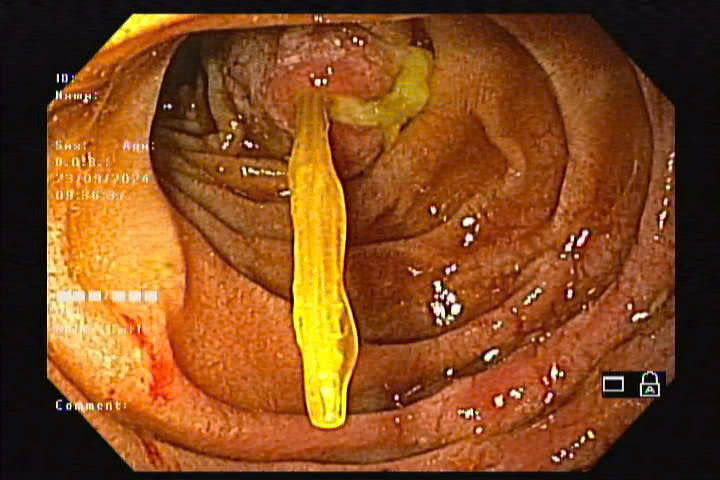

| Tăm tre đâm sâu vào thực quản được lấy ra - Ảnh BVCC |

Qua thăm khám và chụp X-quang nghi ngờ có dị vật, các bác sĩ Khoa Nội Soi đã tiến hành nội soi thực quản – dạ dày – tá tràng bằng ống mềm và phát hiện dị vật là cây tăm tre. Một đầu tăm tre cắm vào thành D2 tá tràng gây thủng tá tràng, tạo ổ áp xe kích thước 10 – 20mm, chảy mủ trắng. Bằng dụng cụ chuyên dụng, các bác sĩ đã lấy que tăm kích thước khoảng 12cm ra ngoài, sau thủ thuật kiểm tra không chảy máu.